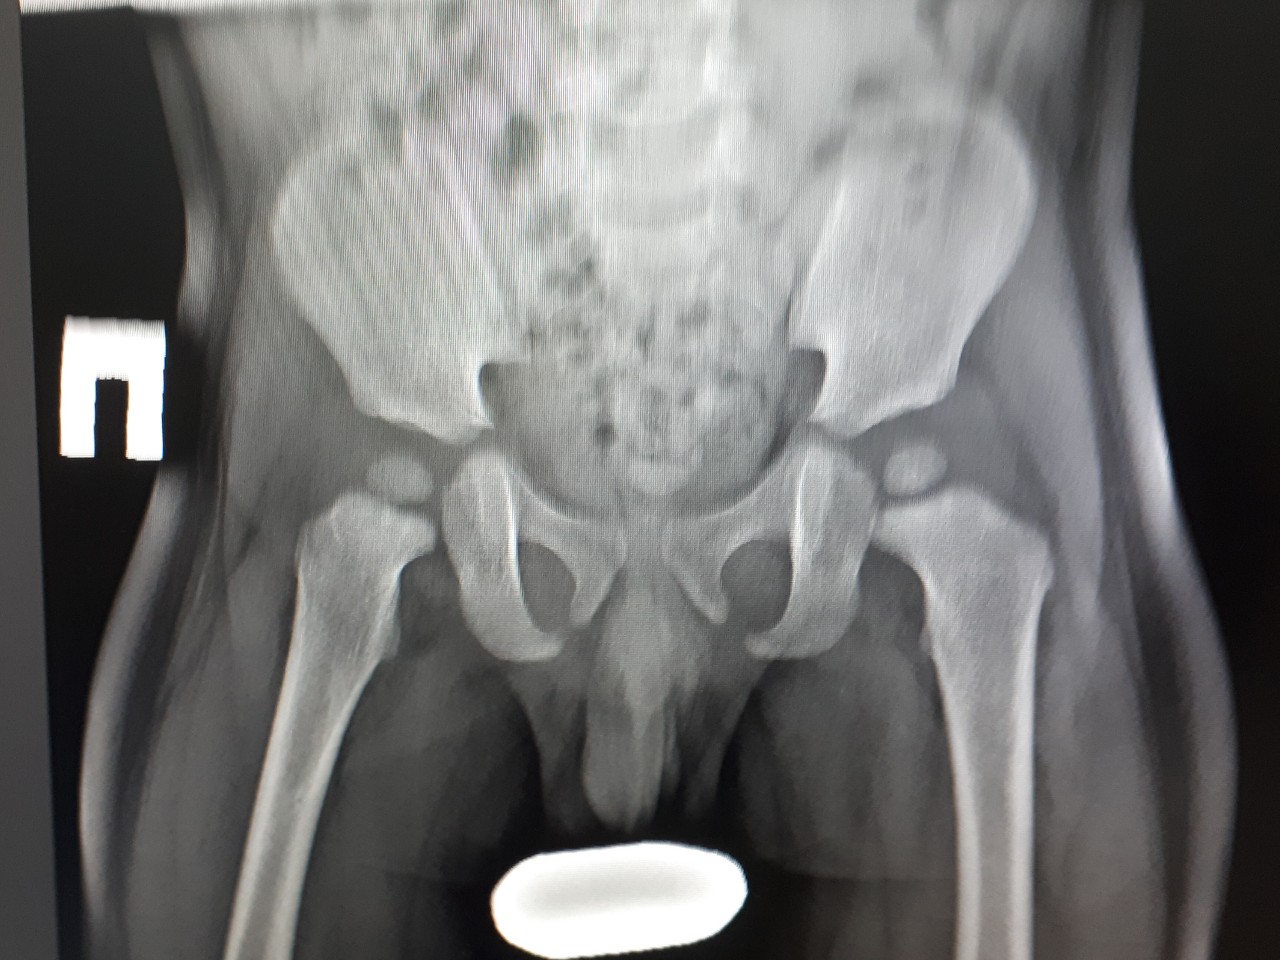

Рентген ТБС: Нормальные показатели

Раздел: Необычные решения